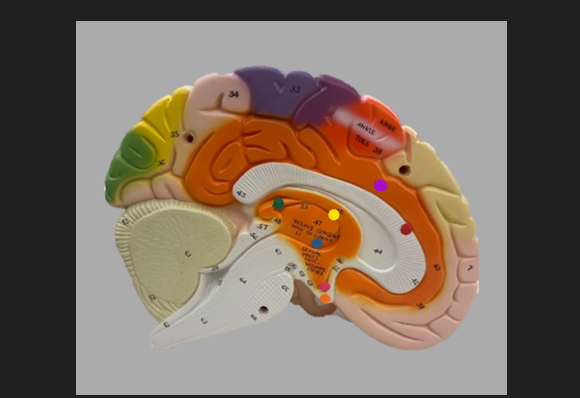

frontal lobe

blue dot

longitudinal fissure

dark green dot

precentral gyrus

pink dot

postcentral gyrus

yellow dot

central sulcus

white dot

parietal lobe

light green dot

Broca’s Area

red dot

Wernicke’s Area

orange dot

occipital lobe

blue dot

parieto-occipital sulcus

blue dot

olfactory tract

red dot

corpora quadrigemina

dark green dot

cerebral aqueduct

blue dot

cerebral penduncles

pink dot

pons

orange dot

medulla oblongata

yellow dot

mammillary body

red dot

corpus callosum

dark green dot

pineal gland

yellow dot

epithalamus

blue dot

thalamus

orange dot

optic chiasm

pink dot

infundibulum

purple dot

cingulate gyrus

yellow dot

pituitary gland

dark green dot

pyramids

red dot

olives

blue dot

optic tract

purple dot

midbrain

green dot

folia

orange dot

arbor vitae

yellow dot

fourth ventricle

red dot

vermis

blue dot

hypothalamus

pink dot

cerebral hemispheres

yellow dot

lateral sulcus

red dot

lateral ventricles

blue dot

hippocampal gyrus